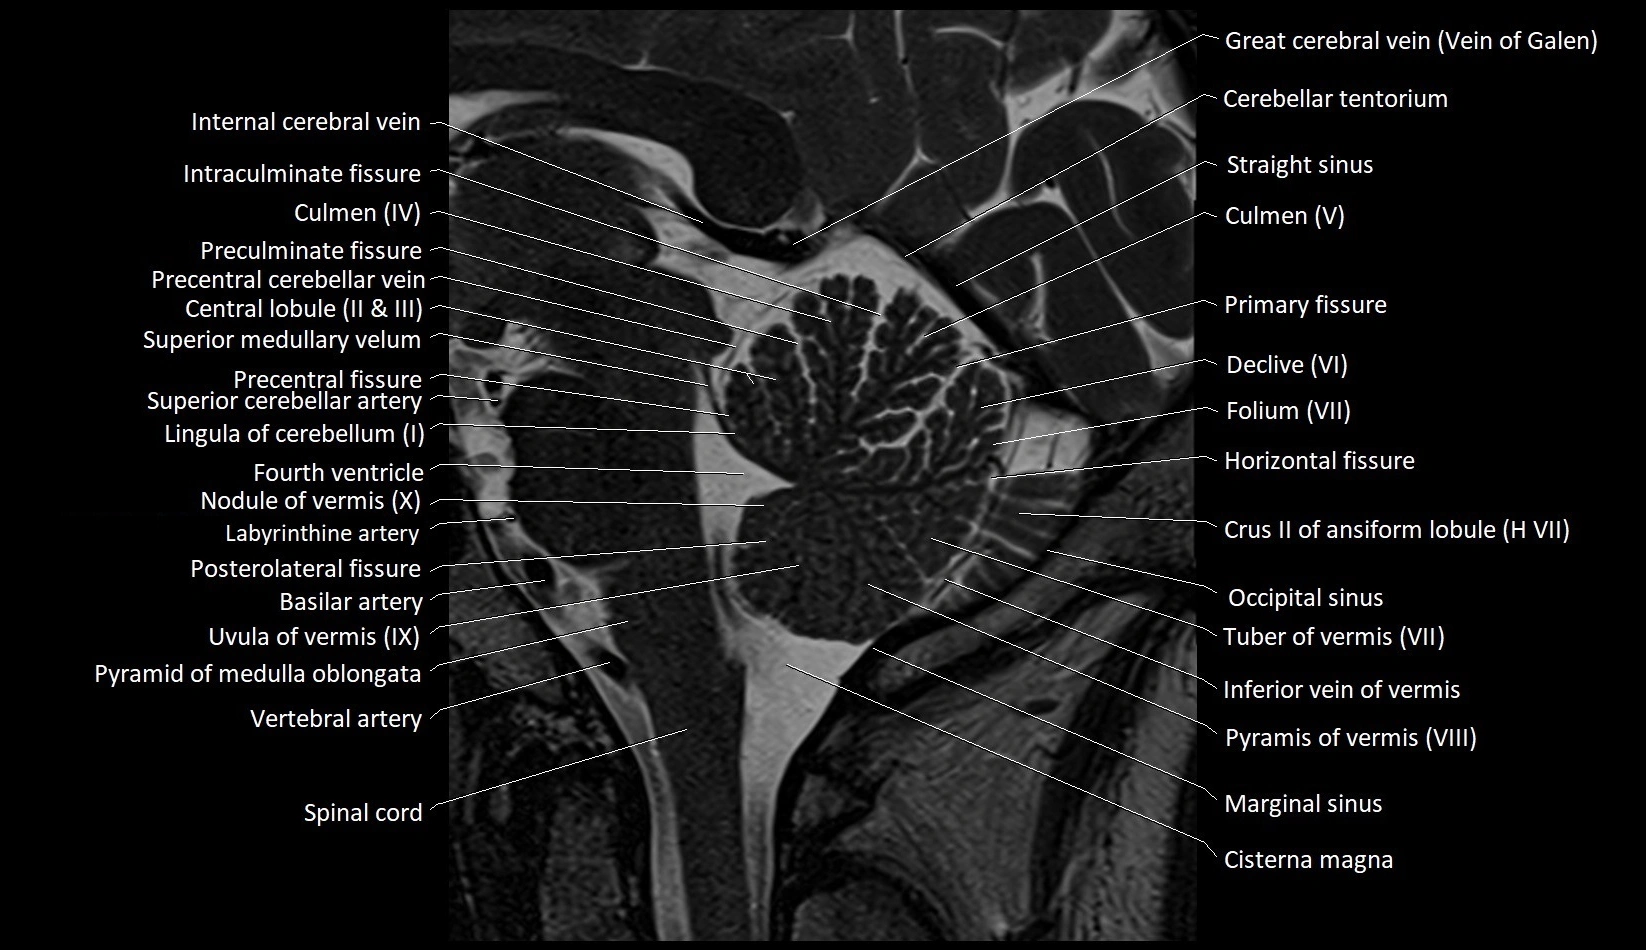

MRI images